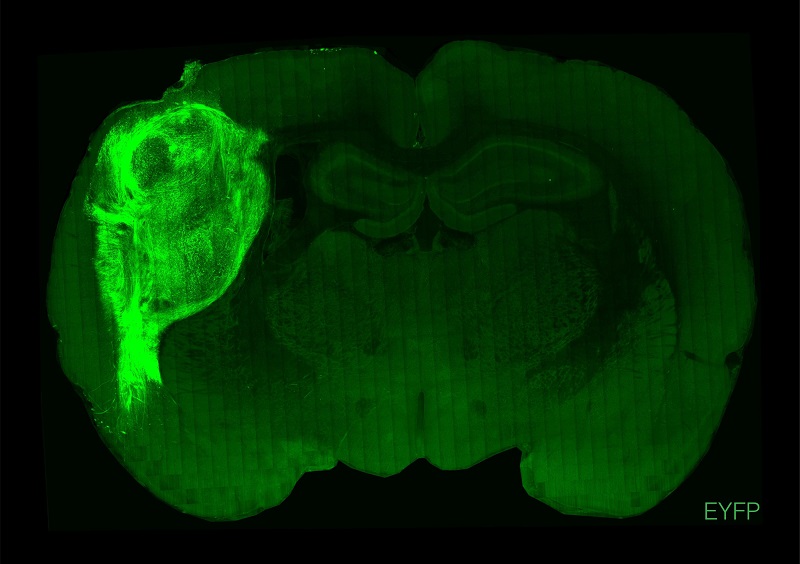

用熒光蛋白標記的人類類腦在大鼠的大腦中。

圖片來源:斯坦福大學

美國斯坦福大學研究團隊此次將人腦類器官植入新生大鼠大腦的體感皮層中,體感皮層是負責從全身接收和處理感覺信息的腦區,包括觸覺。他們發現,該類器官能發育成熟,部分能與神經環路整合,并在大鼠大腦中具有功能性。這種整合讓研究人員能在人細胞的活動與動物習得行為之間建立關聯,證明植入的神經元可以調節大鼠的神經元活動,并能誘導追求獎賞的行為。

此外,在研究人員轉動大鼠胡須時,該類器官中的一組神經元出現了活動跡象,說明植入的神經元能對感覺刺激產生反應。他們還發現,在植入來源于3名蒂莫西綜合征(一種與心臟問題有關的嚴重遺傳病)患者的細胞時,特定的神經元缺陷會被凸顯出來,說明這種植入技術能揭示之前未知的疾病特征。